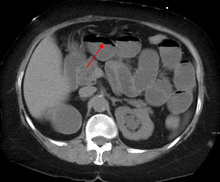

The main diagnostic tools are blood tests, X-rays of the abdomen, CT scanning, and/or ultrasound. If a mass is identified, biopsy may determine the nature of the mass.

Contrast enema or small bowel series or CT scan can be used to define the level of obstruction, whether the obstruction is partial or complete, and to help define the cause of the obstruction.

Some causes of bowel obstruction may resolve spontaneously;[12] many require operative treatment.[13] In adults, frequently the surgical intervention and the treatment of the causative lesion are required. In malignant large bowel obstruction, endoscopically placed self-expanding metal stents may be used to temporarily relieve the obstruction as a bridge to surgery,[14] or as palliation.[15] Diagnosis of the type of bowel obstruction is normally conducted through initial plain radiograph of the abdomen, luminal contrast studies, computed tomography scan, or ultrasonography prior to determining the best type of treatment.[16]